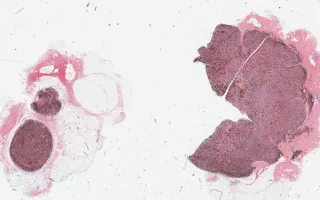

The incisional biopsy demonstrates a multinodular proliferation of densely pigmented melanocytes within the dermis. The bleached H&E slide reveals nuclear atypia and 2 mitoses per mm². The overlying superficial dermis and epidermis are uninvolved. This lesion likely represents a primary dermal melanoma with a blue nevus-like morphology. Alternatively, it may represent a melanoma in which the superficial and radial growth patterns have not been sampled.

This slide shows H&E stain, see related content for Melan-A, HMB45, and bleached H&E stains.